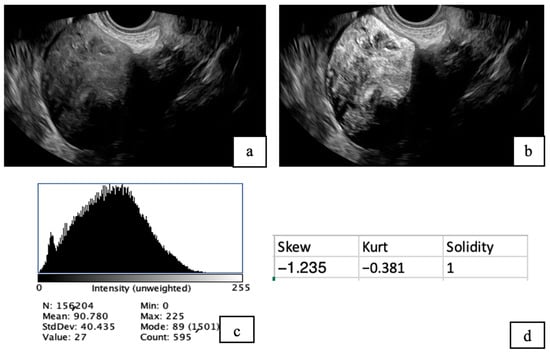

Illuminating the Intricacies: A Comparative Cross-Sectional Sonographic Evaluation of Degenerative Changes in Leiomyomas Through Post-Processing Technique

by Mahasin G. Hassan, Nouf Aldrees, Sadeem Aldawsari, Raghad Alanazi, Noura Alboqami, Maryem Alanazi, Renad Alanazi, Khadejah Alrashidi and Basim S. Almutairi

Diagnostics 2025, 15(23), 2943; https://doi.org/10.3390/diagnostics15232943 - 21 Nov 2025

Abstract

Background: Leiomyomas are benign tumors that may cause symptoms and affect fertility, requiring careful assessment. Magnetic Resonance Imaging (MRI) becomes crucial when ultrasonography results are inconclusive; however, it is expensive and time-consuming. Utilizing post-processing techniques could enhance the ultrasound results. Using ultrasound [...] Read more.

Background: Leiomyomas are benign tumors that may cause symptoms and affect fertility, requiring careful assessment. Magnetic Resonance Imaging (MRI) becomes crucial when ultrasonography results are inconclusive; however, it is expensive and time-consuming. Utilizing post-processing techniques could enhance the ultrasound results. Using ultrasound with Fiji (ImageJ) enables precise evaluation of leiomyoma degeneration and may reduce the need for MRI. Aim: This study aims to evaluate the effectiveness of a post-processing technique using Fiji (ImageJ) to detect degenerative changes in leiomyomas and compare these findings with those obtained from conventional ultrasound and MRI results. Methods: A cross-sectional analytical study was conducted at King Saud Medical City involving 41 females diagnosed with uterine leiomyomas using ultrasound and MRI. Ultrasound images were analyzed using Fiji software to identify degenerative changes and compare results with ultrasound and MRI reports. Results: ImageJ outperformed ultrasound across all diagnostic metrics, with higher sensitivity (84.2% vs. 63.2%), specificity (81.8% vs. 22.7%), and accuracy (82.9% vs. 41.5%). ROC analysis showed superior diagnostic performance of ImageJ (AUC = 0.830) compared to ultrasound (AUC = 0.429), with a significant correlation to MRI findings (p < 0.001). Fibroids with and without degeneration showed no significant differences in Fiji parameters (p > 0.05). Conclusions: Integrating post-processing tools such as ImageJ with ultrasound imaging significantly improves the detection of degenerative changes in uterine leiomyomas, potentially reducing dependence on costly and less accessible modalities like MRI. Future studies should utilize a prospective design with larger sample sizes to strengthen the validity and generalizability of these findings. Full article

(This article belongs to the Special Issue Advanced Ultrasound Techniques in Diagnosis)

Show Figures

Figure 1